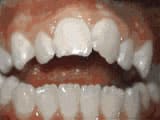

Missing lateral incisors

Before

AfterThis woman’s lateral incisors were missing since birth. She had braces for 20 months to move the teeth into their correct positions, then the missing teeth were replaced with bonded “Maryland” bridges.